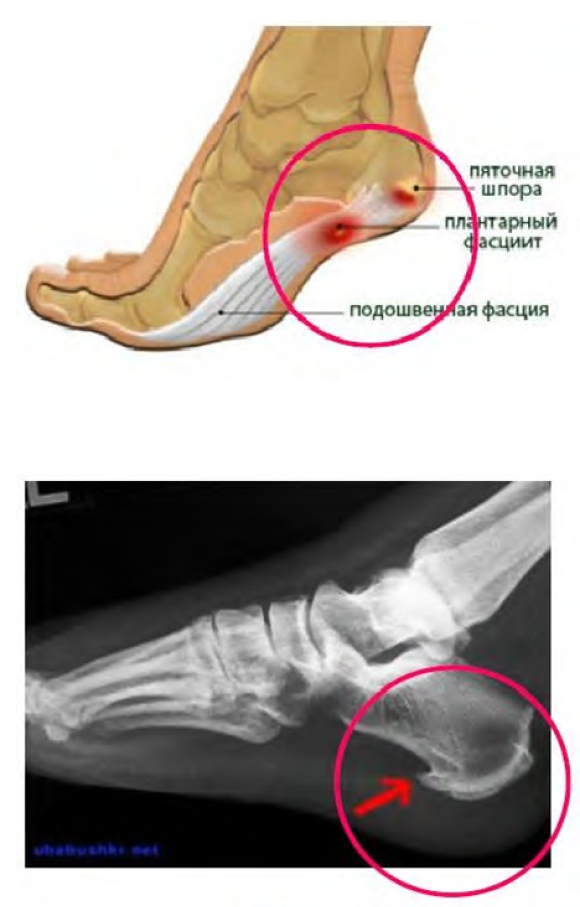

Преимущества и особенности индивидуальных стелек при пяточной шпоре:

Показания к применению стелек ORTMANN PRO Comfort: